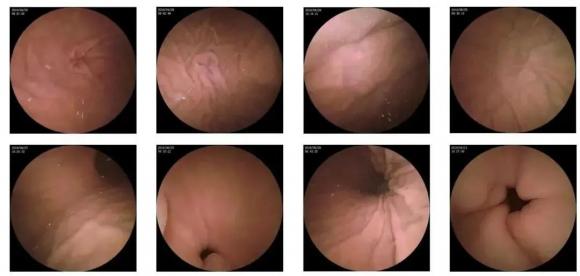

10—15分鐘即可完成賁門、胃底、胃體、胃角、胃竇、幽門等解剖部位觀察,讓胃部檢查更高效。更為重要的是,檢查全程無痛、無創、無麻醉,避免了傳統插管胃鏡帶來的生理痛苦。

膠囊機器人的專利三鏡片鏡頭,可深入觀察0.04毫米微小單位,每秒可拍高達4張高清醫學照片。

醫生通過智能閱片系統,可自動對海量圖像識別過濾,智能篩選,能有效提升醫生檢查及閱片效率。

任何細微的胃部病變,如胃潰瘍、胃出血、息肉等都無所遁形,盡在大圣磁控膠囊式內窺鏡系統的掌握之中。